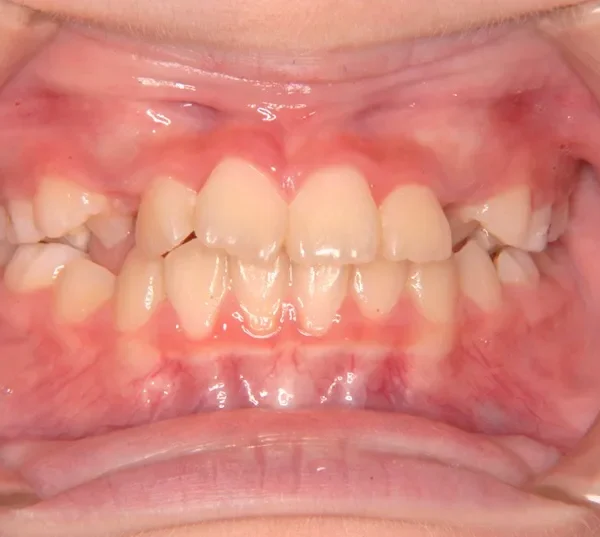

• 初診

上下がガタガタで犬歯の生えるすきまがありません。

このままだと犬歯の生えるスペースがありません。放っておくと犬歯が上の位置からはえ、牙のようになってしまいます。

乳歯があるうちは上下オリジナル固定装置を利用し、永久歯が生えそろったらマルチブラケット装置を利用して治療しました。

治療回数35回、5年9ヶ月の治療期間で矯正治療を終了しました。